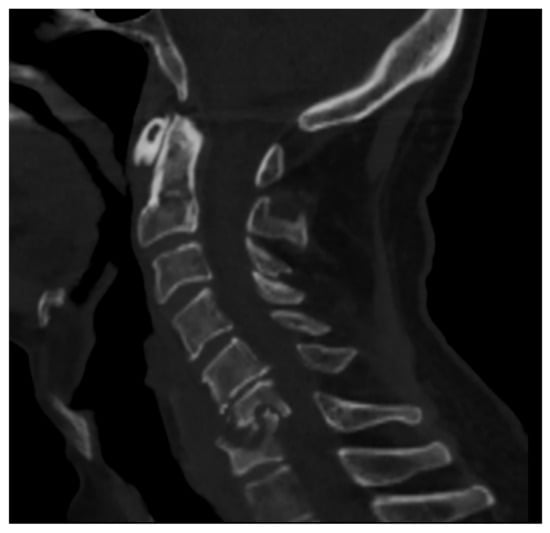

Figure 1. CT of the cervical spine (sagittal reconstruction) of a middle-aged man (HIV+) affected by spondylodiscitis in the C6–C7 tract of the cervical spine complicated by myelopathy.

The lumbosacral region is involved in 52–58% of cases, the thoracic spine in 26–35% of cases, and the cervical spine in the remaining 10–22% of cases (Figure 1) [12].